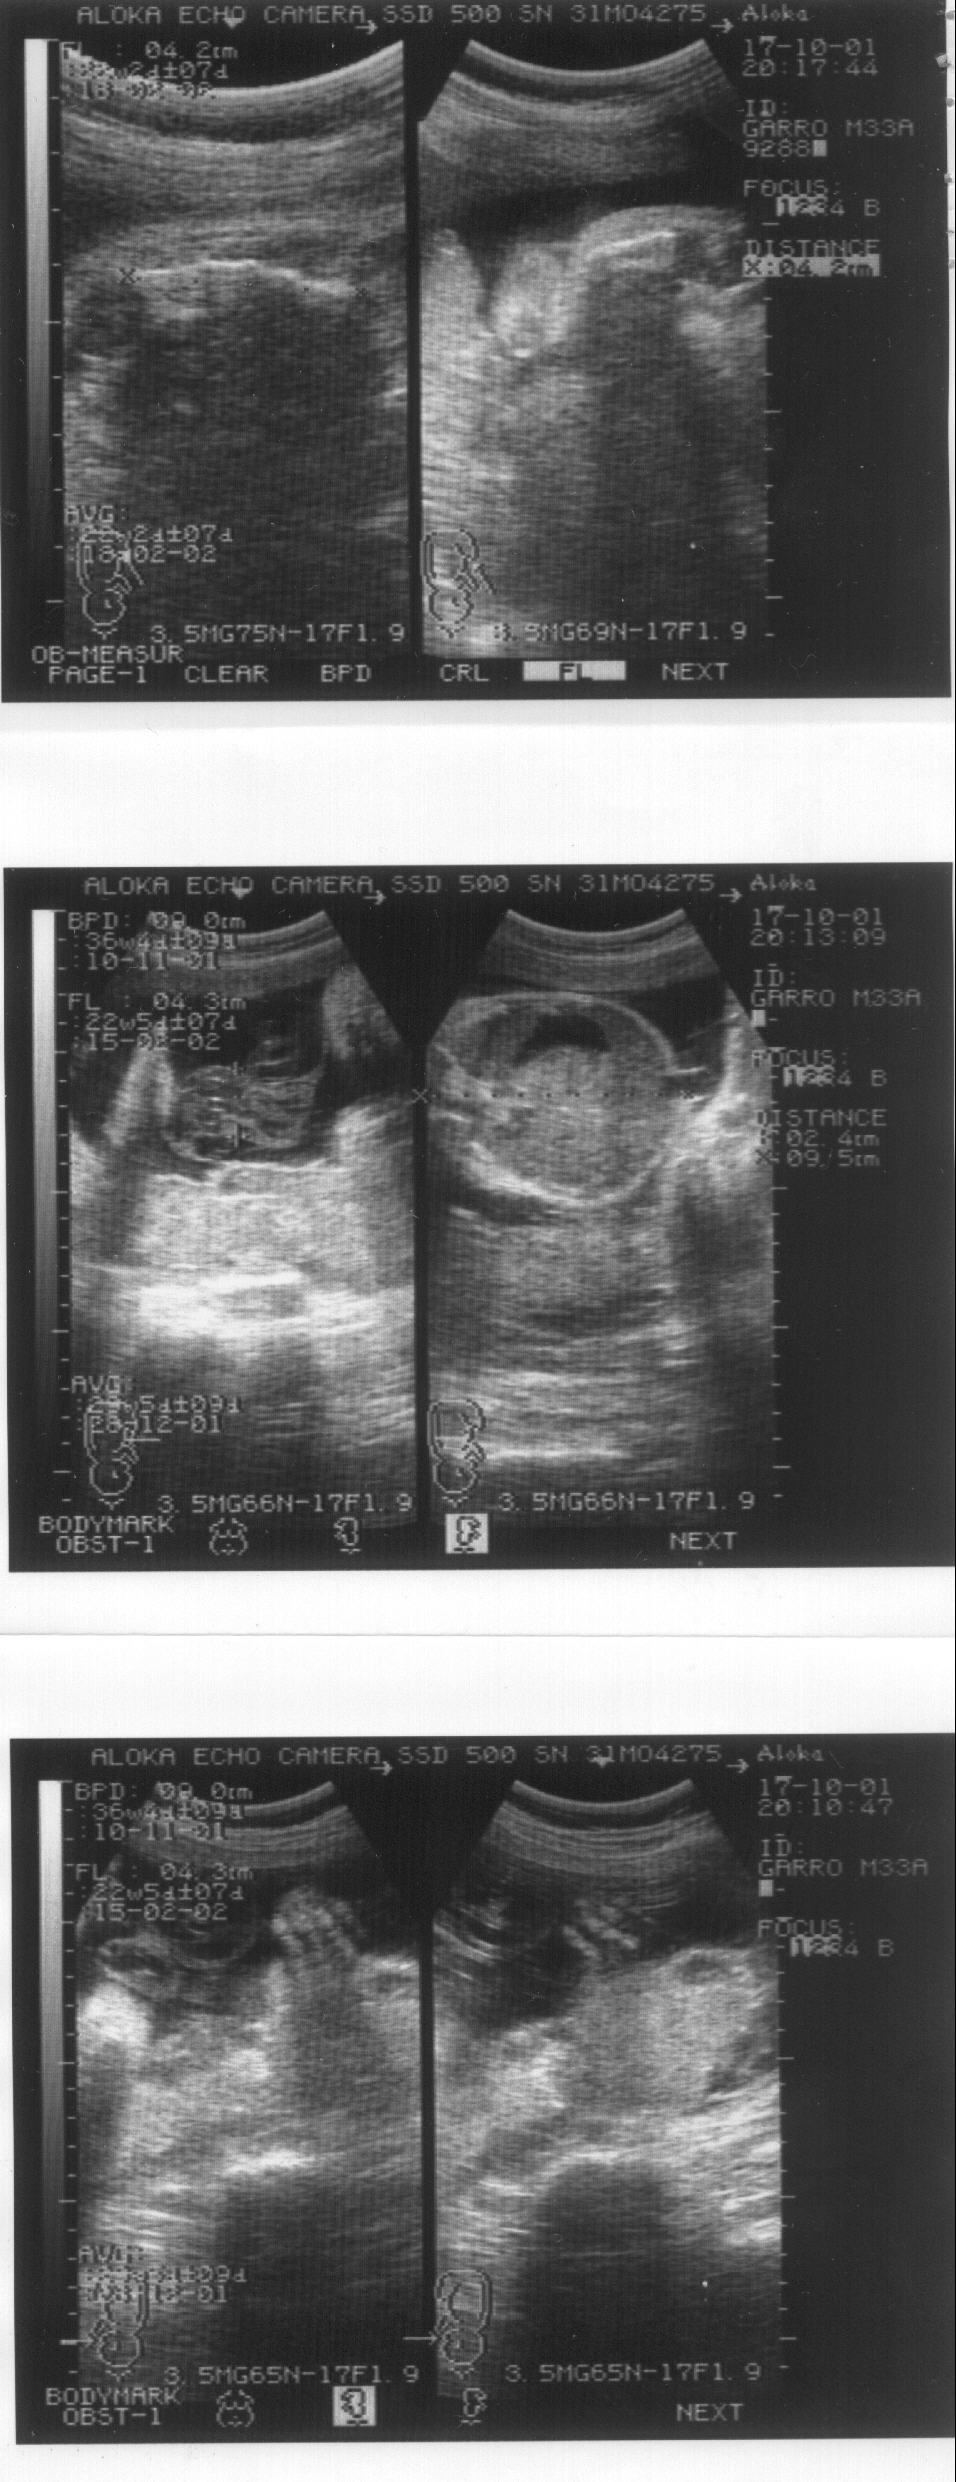

Un caso de osteogénesis imperfecta letal. Octavo mes de embarazo. Imagen 4/4

Imagen de la ecografía